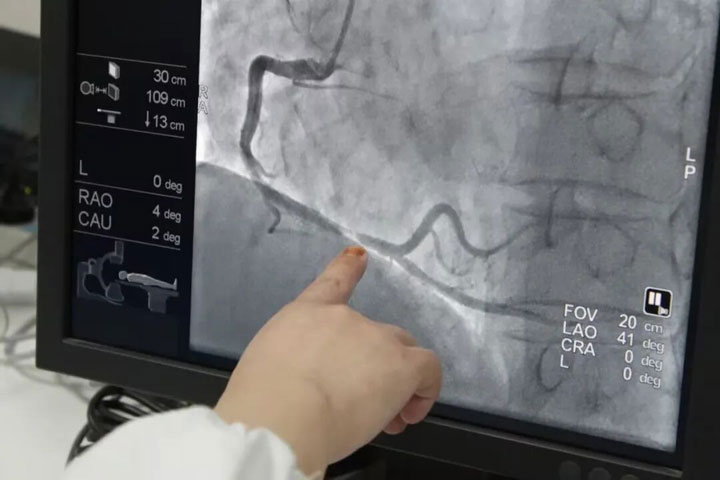

冠脉造影(微创):血管的“实时电影”

诊断冠心病的“金标准”,通过从动脉插管注射造影剂,利用血管透视机实时拍摄动态视频,能精准判断血管狭窄程度,15-20分钟左右即完成,优点是诊断精准,可以同步开展支架植入等治疗,缺点是属于侵入性操作,需要局部麻醉,术后需住院观察。